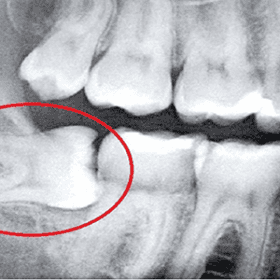

- Thăm khám trước nhổ: Chụp X-quang để đánh giá vị trí răng khôn, từ đó bác sĩ sẽ tư vấn phương pháp phù hợp.